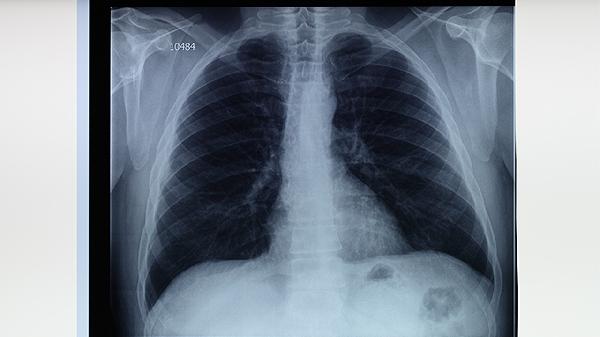

治疗期间需保证每日摄入优质蛋白如鱼肉蛋奶,进行适度有氧运动如太极拳或步行以增强肺功能。严格遵医嘱完成全程治疗,定期复查胸部影像与痰菌检测,治愈后仍需每半年随访1次持续2年。注意居室通风消毒,密切接触者应进行结核菌素试验筛查。